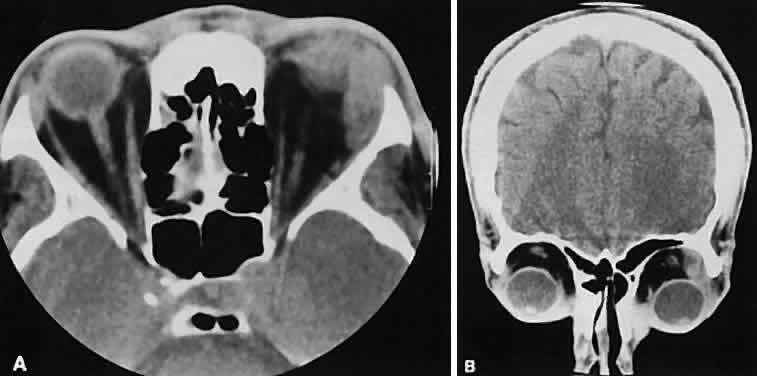

An appreciation for the various pathologic processes that affect the orbit is facilitated by an understanding of the normal orbital anatomy (Fig. 1). The orbit is a pyramid-shaped bony structure bounded inferiorly by the maxillary sinus, medially by the ethmoidal sinus, and superiorly by the frontal sinus. The sphenoidal sinus is situated posteriorly along the medial orbital wall and has a common wall with the optic canal. The lacrimal gland lies within its fossa located in the superior temporal aspect of the orbit and can be seen on both axial and coronal views.

The extraocular muscles (EOMs), with the exception of the inferior oblique, originate from the anulus of Zinn in the orbital apex. The inferior oblique takes its origin from the frontal process of the maxilla and is seen occasionally on CT imaging. The superior oblique, after originating from the anulus, courses along the superior nasal orbital wall just above the medial rectus muscle before passing through the trochlea. The rectus muscles conveniently form a muscle cone, which is sometimes helpful in terms of differential diagnosis. Before thinner axial slices and multiplanar imaging were available, an enlarged inferior rectus muscle often was imaged as an apical mass, especially if dysthy-roid optic neuropathy was present. The importance of imaging from two different planes cannot be overemphasized in this situation.

The superior ophthalmic vein (SOV) is an important vascular structure to recognize. It begins in the superior nasal quadrant near the trochlea before coursing posteriorly and laterally beneath the superior rectus muscle, exiting the orbit through the superior orbital fissure. Drainage is into the cavernous sinus. Asymmetric enlargement, especially in the presence of an ipsilateral cavernous sinus enlargement, suggests a vascular anomaly, which may require selective carotid angiography for further definition. Enlargement of one or multiple EOMs in this setting is likely. The SOV also may be enlarged as a result of any process impeding drainage from the orbital apex, such as dysthyroid orbitopathy or metastatic disease.

The optic nerve occupies the central intraconal space. By necessity, the nerve has a certain amount of slack, which is necessary to permit movement of the globe. In the axial plane, the optic nerve has an undulating course and thus may appear thicker or thinner as a result of partial volume averaging as it passes in and out of the axial plane. It is imperative to recognize this normal pattern for proper interpretation of axial images.

The optic nerve itself is invested by the same meningeal layers that cover the brain, and the intracranial space may extend along the course of the optic nerve to the back of the globe. Enlargement of this space may be recognized as pseudomeningoceles of the optic nerve sheath. It is sometimes possible to tell whether the nerve, the sheath, or both are enlarged by CT scanning, although MRI affords the better view.